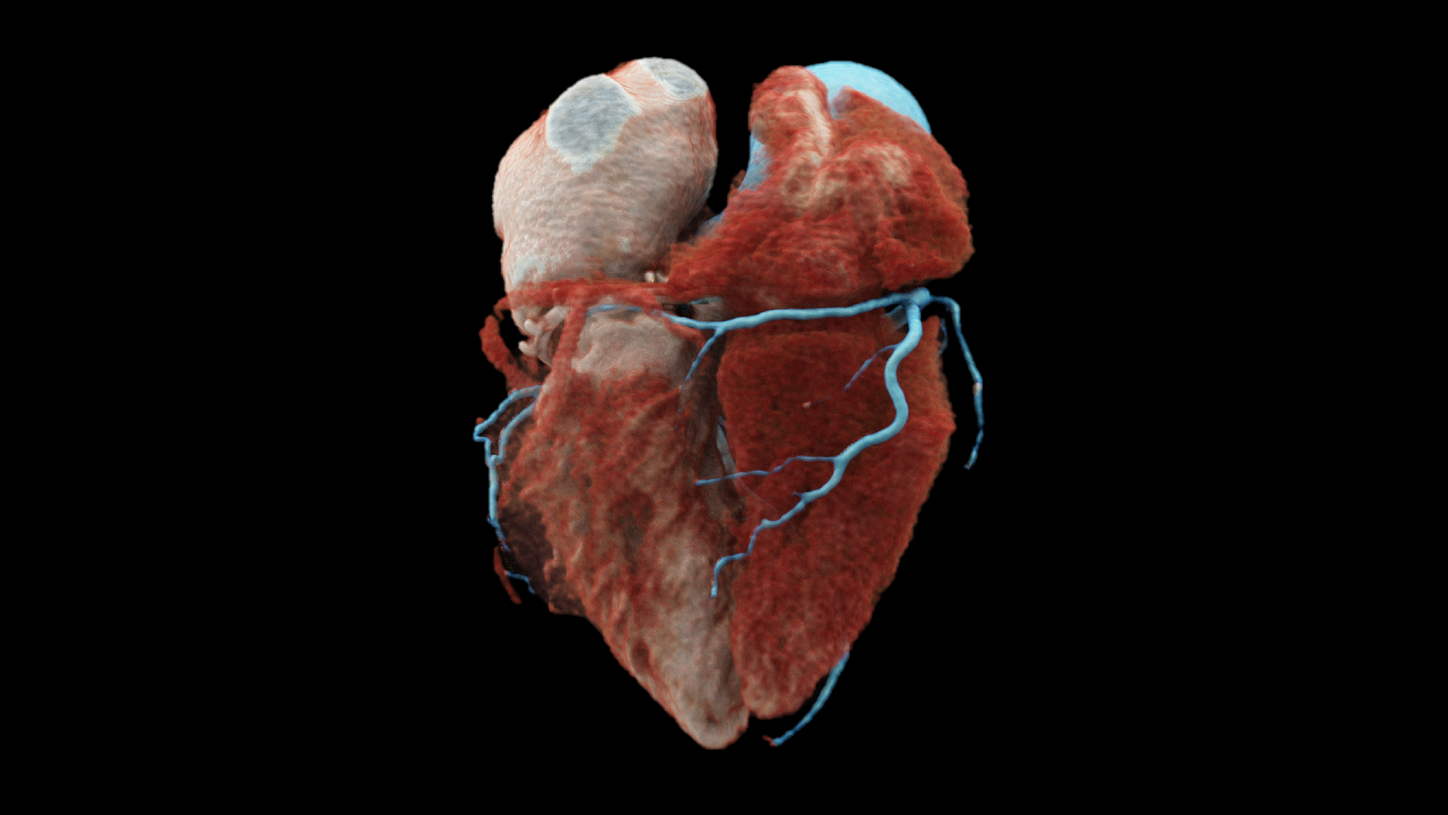

NAEOTOM Alpha allows spectral imaging for cardiac scans

NAEOTOM Alpha

with Quantum Technology

NAEOTOM Alpha® offers high resolution in cardiac imaging to

• see small details in coronary CTA;

• identify more details in coronary plaque evaluation;

• offer high resolution at low dose in all standard CT angiography protocols.